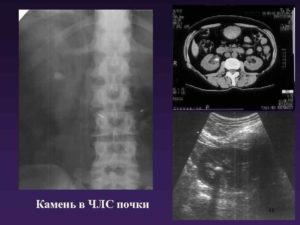

Бывает, что у пациента обнаруживают камни в почках – в этом случае лечение проводиться с помощью хирургического вмешательства, после которого человек полностью выходит на поправку. Также известны случаи, когда уплотнение синусов почек имеет злокачественную опухоль, при которой также назначается операция и курс химиотерапии.

Результаты ультразвукового исследования организма не всегда могут показать верную картину происходящего в нашем организме, поэтому для более верной ситуации стоит пройти другие обследования. К примеру, УЗИ мочекаменной болезни далеко не всегда может дать верный результат, так как образования соли маленьких размеров УЗИ может не распознать.

Уплотнение синусов обеих почек наблюдается при уролитиазе – урологическом заболевании, которое сопровождается камнеобразованием в органах мочевой системы. Нарушение обмена органических и минеральных веществ ведет к кристаллизации солей кислот – этандиовой, фосфорной, мочевой. В результате в ЧЛС возникают мелкие камешки.

МКБ чревата образованием крупных камней в мочевой системе. Наиболее опасны коралловидные конкременты, которые заполняют собой весь объем ЧЛС.

Микролиты обеих почек выводятся из организма с мочой. При прохождении по чашечкам и лоханкам они травмируют слизистую, что приводит к неинфекционному (асептическому) воспалению. На уплотнение синусов почек у женщин и мужчин указывают: